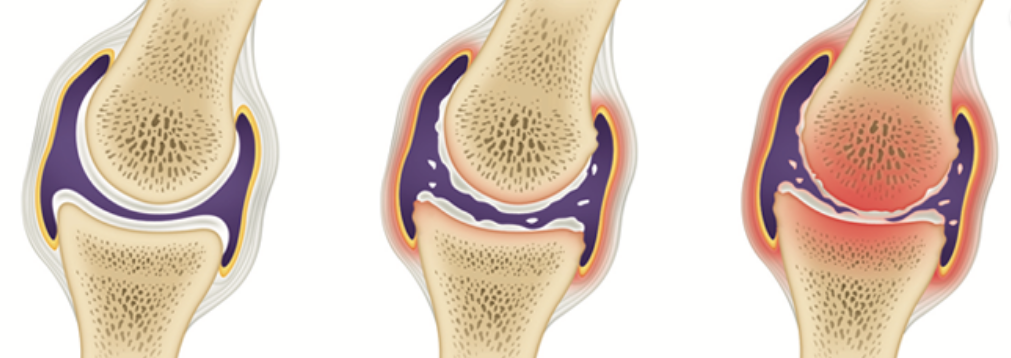

관절염을 예방하고, 관절 내 염증을 줄이는 방법에는 적정한 체중을 유지하고, 위에서 말씀드린 근력 운동을 꾸준히 하는 것 외에 관절에 좋은 음식을 섭취하는 것으로도 도움을 받을 수 있어요.

12. 관절 영양제

글루코사민, MSM, 콘드로이친과 같은 관절 영양제는 연골 생성에 도움이 된다고 합니다. 이 성분들은 관절을 구성하는 성분인데, 염증으로 발생하는 통증을 완화시키고, 염증을 가라앉히는 효능이 있다고 알려져 있습니다. 따라서 관절이 좋지 못하신 분들이라면 글루코사민, MSM, 콘드로이친과 같은 관절 영양제도 함께 섭취해주신다면 더욱 좋습니다.

이미 망가진 관절은 되돌리기가 쉽지 않아요. 망가지기 전에 소중한 관절을 관리하고 보호해야겠습니다.

"연골은 지우개와 같아. 한번 닳아 없어진 연골은 다시 생성되지 않아. 미리미리 관리하는게 중요해 "